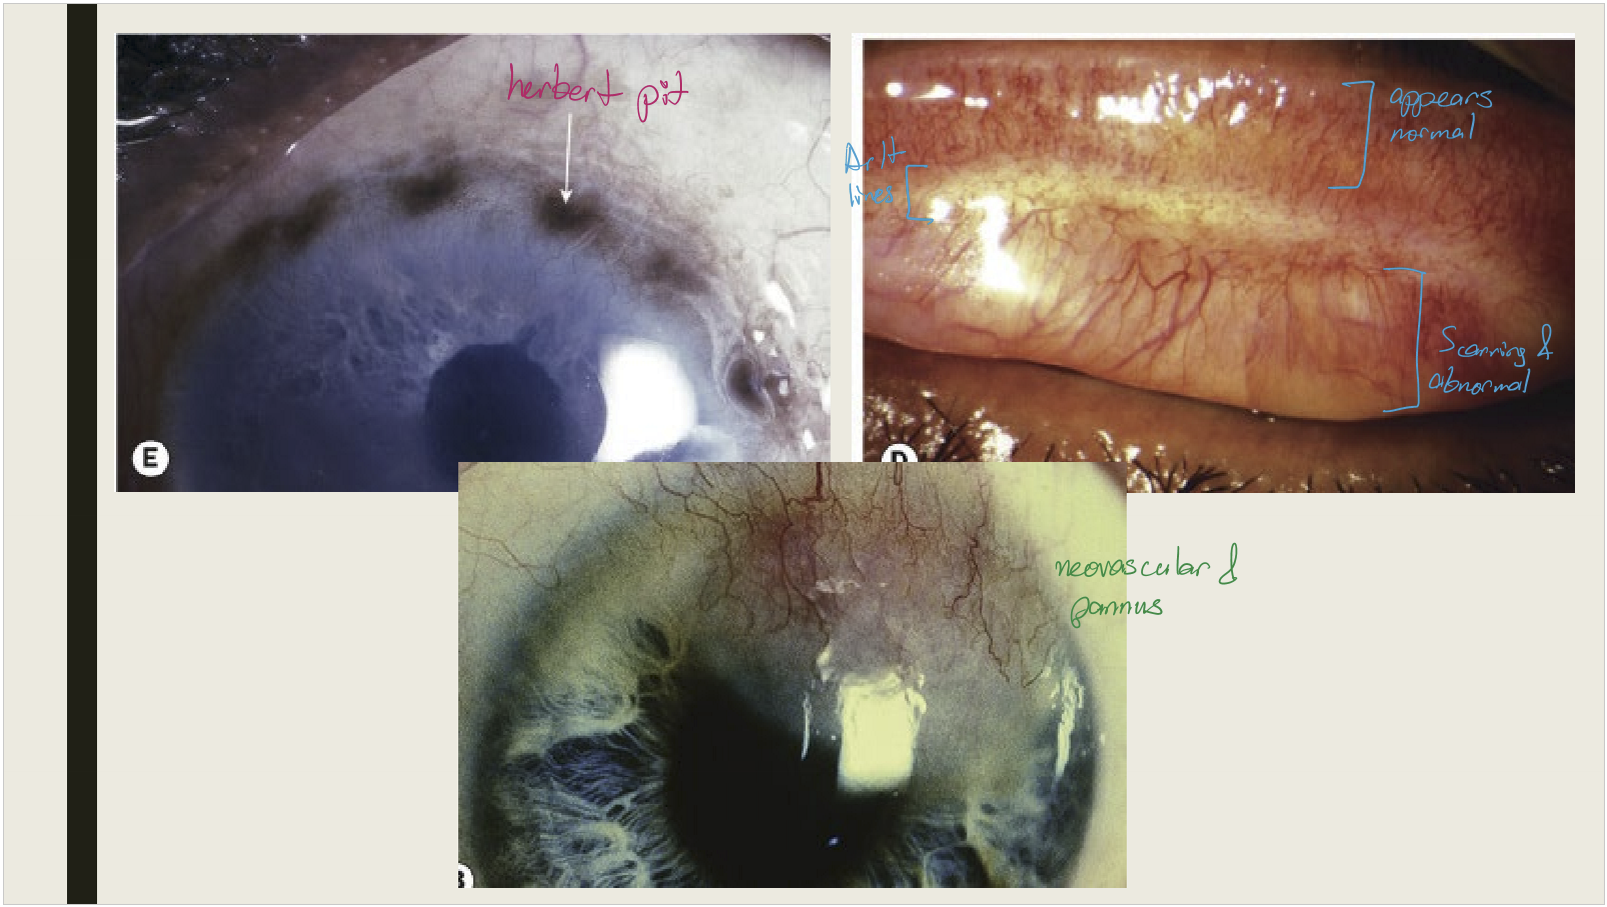

What conjunctival changes occur in cicatricial trachoma?

Conjunctival scarring

• Mild infection: linear or stellate scarring

• Severe infection: broad confluent scared (Arlt lines)

• Superior tarsal effected more then other areas of conjunctiva

<p>Conjunctival scarring </p><ul><li><p>Mild infection: linear or stellate scarring</p></li><li><p>Severe infection: broad confluent scared (Arlt lines)&nbsp;</p></li><li><p>Superior tarsal effected more then other areas of conjunctiva&nbsp;</p></li></ul><p></p>

What happens to superior limbal follicles after they resolve in cicatricial trachoma?

They leave shallow pits (Herbert pits)

<p>They leave shallow pits (Herbert pits)</p>

What are the corneal and eyelash changes seen in cicatricial trachoma?

Corneal opacification with vascularization; trichiasis and distichiasis

<p>Corneal opacification with vascularization; trichiasis and distichiasis</p>

What type of conjunctival reaction is seen in active trachoma?

Mixed papillary + follicular reaction, mucopurulent discharge, superior epithelial keratitis, pannus formation

<p>Mixed papillary + follicular reaction, mucopurulent discharge, superior epithelial keratitis, pannus formation</p>